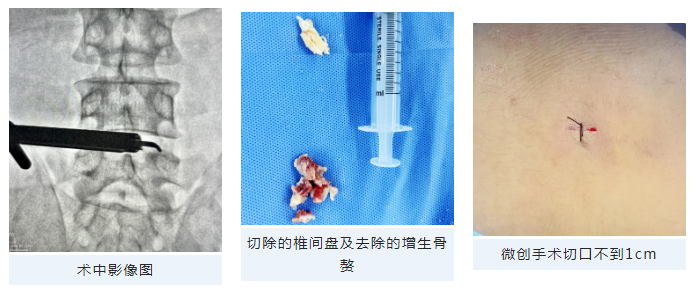

6月16日,在脊柱病医院院长郝定均及脊柱病医院腰椎病区主任刘团江的指导下,杨俊松副主任医师团队成功实施西安市红会医院首例腰椎管狭窄症患者超声骨刀辅助下单侧椎板入路双侧椎管减压(ULBD)手术,标志着北院区脊柱病院开启腰椎间盘突出症微创诊疗的新征程。

“为了保证手术效果和安全性,我们在手术中特别引入了超声骨刀”杨俊松副主任医师介绍,“超声骨刀可根据不同组织的密度改变输出功率,对密度高的骨组织输出大功率以达到切骨的目的,但对周围硬膜及神经等伤害相对较小。杨俊松副主任医师积极完成相关检查后,当即为患者安排手术,确保患者早日缓解疼痛。

术后当天,患者术前下肢疼痛麻木症状缓解,无其他不适,复查核磁硬膜囊膨隆,减压效果满意。

ULBD手术是目前治疗双侧症状腰椎管狭窄症患者的最佳选择之一。首例超声骨刀辅助下ULBD手术是脊柱病院立足北院区,探索腰椎退行性疾病微创治疗新的开始,标志着西安市红会医院在脊柱微创手术方面已经拥有较高水平。通过智能化设备的引入,将使脊柱微创手术插上腾飞的翅膀,能够满足更多患者的广大医疗需求!